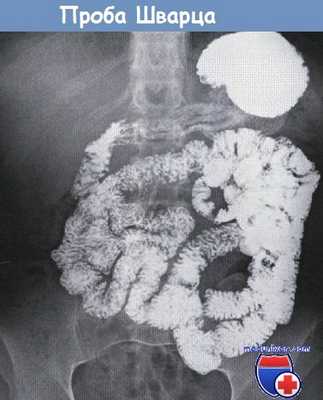

Введение рентгеноконтрастного вещества в верхние отделы ЖКТ (через рот или назогастральный зонд (НГЗ)) с получением серии рентгенограмм для исследования продвижения контраста по тонкой кишке в толстую.

а) Преимущества пробы Шварца:

• Оценка анатомических особенностей, конфигурации, диаметра, длины (например, после предшествующих резекций), стриктур, свищей, изменений слизистой и т.д.

• Оценка функции: время пассажа, замедленное продвижение контраста.

• Выявление уровня обструкции.

б) Ограничения пробы Шварца. Ограниченные возможности для оценки состояния слизистой по причине наложения петель друг на друга.